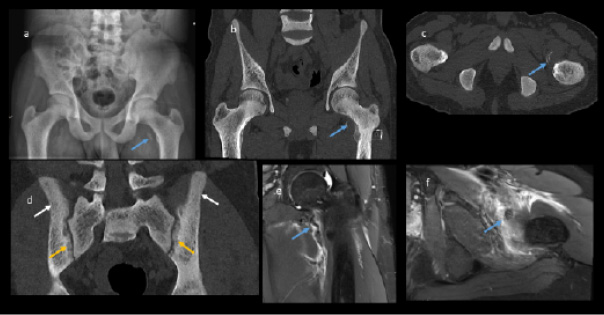

Plain radiographs showed significant bilateral olecranon soft tissue swelling with faint curvilinear ossification proximally suspicious for bilateral avulsion fractures. The ultrasound confirmed loss of tension of the triceps tendon attached to a small bone fragment on the right (Figures 1 and 2). Pelvis radiographs showed an avulsion fracture of the lesser trochanter of the left femur and marked bony sclerosis consistent with renal osteodystrophy. CT of the left elbow indicated a small bony fragment in the distal triceps tendon area with cortical irregularity and significant soft tissue swelling. CT pelvis revealed diffusely increased bone density, subchondral erosions, and resorption at the sacroiliac joints as well as femoral necks consistent with secondary hyperparathyroidism due to end-stage renal disease. MRI of the hip showed generalized skeletal sclerosis along with avulsion of the left iliopsoas tendon with proximal retraction and adjacent soft tissue oedema (Figure 3).

The overall diagnosis included bilateral triceps avulsion fractures with minimal retraction on the right side and significant retraction on the left, a left iliopsoas tendon avulsion with retraction, and florid features of renal osteodystrophy associated with ESRD. The patient underwent surgical repair of the left olecranon avulsion fracture (Figure 1d) while the right olecranon and left lesser trochanter avulsion fractures were managed conservatively.